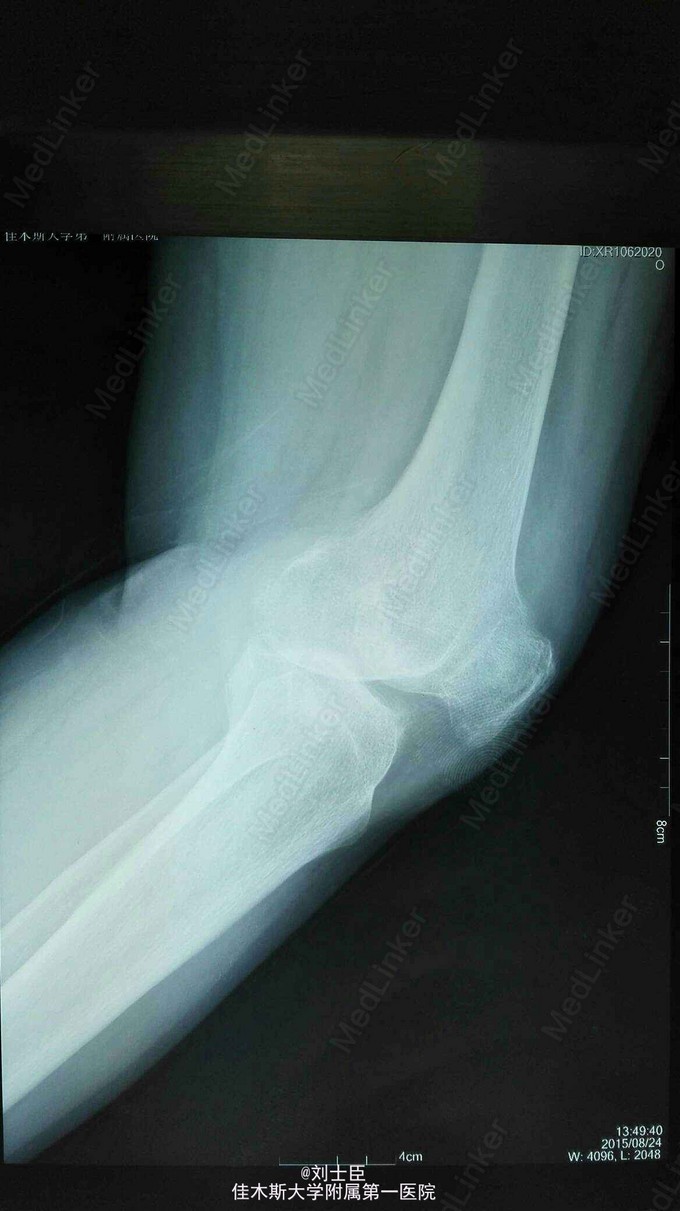

xx,女,54岁。左膝疼痛伴活动受限5年加重1个月。上下楼困难,走平路500米跛行。

左膝内侧压痛明显,伸直10度,屈曲100度。蹲起困难。过伸过曲实验阳性。

左膝关节骨性关节炎。 膝关节镜清理术加腓骨截骨术。